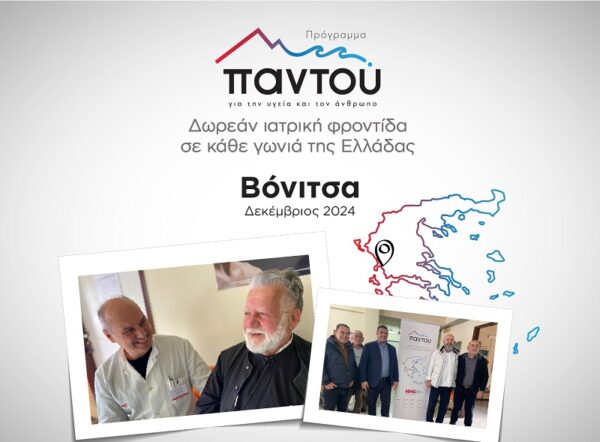

ΥΓΕΙΑ